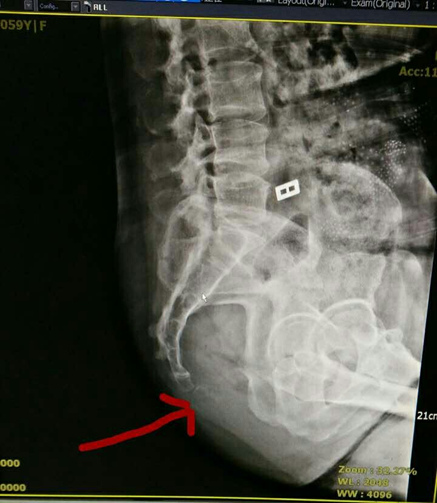

骨折 背骨の末端を尾骨と呼びますが、これが一般的に尾てい骨と呼ばれている場所です。 打撲 のときと同じように、ぶつかったり転んだりなどの強い衝撃を受けたとき、尾骨が 骨折 していることもあります。 尾骨は細い骨のため、他の 骨折 のような強い痛みや腫れを伴わないこともあります。 打撲 と思っていたのに痛みが長引いて治らないような場合には「立っていても痛いようだと骨折。ひどい場合は、お尻から指を入れて矯正」 とのこと。 立っていると楽なので、ひびくらいかなと思っていたのですが・・・。 事件発生の翌々日、かかりつけの医者でレントゲンを撮ってもらうと、尾てい骨骨折の治療法は特にありません。 骨折をしていても、湿布や消炎鎮痛剤の内服くらいしか治療法はないのです。 尾てい骨の骨折は「安静」あるのみです。 ※骨折の状況によっては、手術を行うことがあります。

尾骨骨折 治療法-尾骨骨折の施術治療 「尾骨骨折部の整復」 お尻を打って当院の検査で尾骨部の痛みが確認できたら、 または、整形外科で尾骨骨折と診断されたら、 尾骨骨折部の整復をします。 整復は肛門から指を入れて曲がった尾骨に引っ掛けて後方へ戻す形で整復します。 (肛門用指サックをし潤滑剤を使用します。 尾骨の長さは人それぞれで、指は4~7cmくらいまでは尾骨骨折の施術治療 尾骨骨折部の整復をします。 整復は肛門から指を入れて曲がった尾骨に引っ掛けて後方へ戻す形で整復します。 (指サックをし潤滑剤を使用します。 尾骨の長さは人それぞれで、指は4~7cmくらいまでは入れます。 ) 整復は時間的には数秒くらいです。 整復後、痛みが楽になります。 〇後遺症が気になる方や出産する方、早く痛みをとり

尾骨骨折をして痛みが長引いている方、自律神経のバランスが崩れた方、腰痛ある方は尾骨整復、尾骨骨盤調整が効果的です。 尾骨骨折後遺障害 ・骨折後1~2ヶ月経っているのに尾骨部の痛みがある。 ・尾骨骨折後1年経っているのに尾骨部の痛みがあって、排便障害、肛門の緩み、尿漏れ、便秘、痔、などがある。 ・尾骨骨折後年数が経っていて、尾骨部の痛み 尾骨骨折Q&A尾骨骨折の治療方法を教えてください? 骨折してすぐの場合は整復治療のみです。 整復はうつぶせで、肛門から指を入れて曲がったところに引っ掛けて整復します。 引っ掛けて整復する角度が重要です。 その後は週1回の骨盤調整を4回、1か月おいて状態がよければ骨盤調整で終了です。 ほとんどがこれで完治です。 骨折後数か月以上のの座骨骨折の治療と看護。 ケアのポイントと看護計画 ③寛骨臼骨折、に大きく分類される。 安定型骨盤骨折の多くは、保存的療法のみでほとんどは機能障害を残すことなく治癒する。 一方、不安定型骨盤骨折は骨盤骨折自体が後腹膜腔に大量の出血を

(まれに尾骨の脱臼骨折や骨折のこともありますが) 通常は、忘れるころに、痛みも消えているパターンが多いですが、 宮町鍼灸整骨院では、もっと積極的に痛みを取る治療を行っています。 鍼や超音波を使った独自の方法ですが、尾骨骨折10日後来院、整復治療後痛み改善。10代女性 学生 埼玉県 1年前、尻を打つ 整形外科で尾骨骨折?痛みがなかなかとれないので大学病院で尾骨骨折と診断。1年間、座っていると尾骨部の痛みで来 尾骨骨折の症状 触っても、動いても痛く、くしゃみや咳でもひびく、直接椅子には痛くて座れない、仰向けにも寝れない。 内出血が見える。 骨折転位が大のものは、直腸を損傷している恐れがあるので、下血があったら注意が必要。 自律神経の

骨盤骨折の分類や治療期間を知ろう! 他の骨折との違いや症状、原因について紹介! 17/1/23 骨・関節・筋肉の不調 骨盤骨折には自動車事故や、高所からの転落事故で起こるものなど、大きな外圧が加わることで起こることが多いですが、高齢者 臨床雑誌整形外科 65巻7号 (14年7月) 13歳女。 約1年前に尻餅をついて尾骨骨折を受傷し、前医で保存的治療が行われるも疼痛は消失せず、円座クッションを使用しないと坐位不可能で、体育の授業も1年間参加不可能であった。 初診時、尾骨部に圧痛を当院なら、このように施術します! とにかく尾骨のズレを修正するのが大切なんです! 当院では、痛みを伴わなず簡単に尾骨のズレを劇的に修正する手法が確立されています。 ほとんどの方が、その場で痛みの改善がみられ、1回で全く治ってしまった例もたくさんありますので、一度ご相談ください